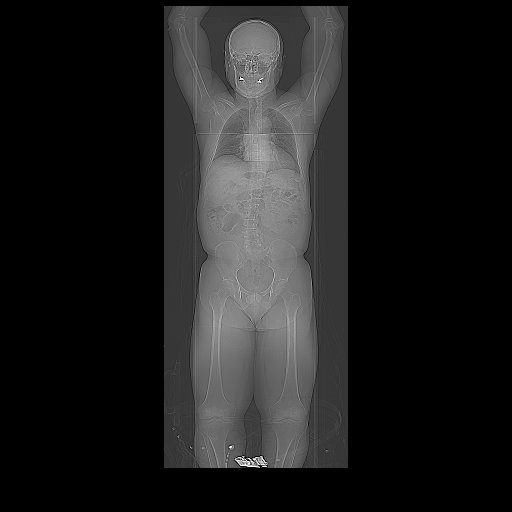

After getting my prostate gold-plated, having a seat cushion

of treatment, I needed to get sophisticated scanning, also known as “mapping”

or “radiation simulation,” done. From

the scans, my radiation oncologist, Dr. Sayan, could “design” the radiation

specifically to target my particular cancer. He had mentioned he would need two weeks to do

this. The fact that Dana-Farber/Mass

General has the most sophisticated scanning equipment was a major reason I

chose to go to Boston to get treated.

![]() |

The scanning machines used looked something like this |

Undergoing radiation "simulation" (I did not require a mask)

The imaging itself was, again, uneventful. By now, I’d been through a few scans,

including long ones, noisy ones, and scans with open or closed tubes, so these

were not anything new.